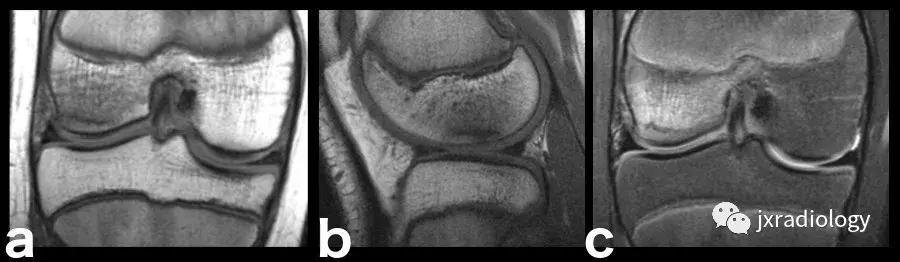

图2:骨性关节炎(OA):男,58岁,股骨内侧髁负重区有软骨缺损,伴有边缘小骨赘和继发性软骨下骨髓水肿。骨性关节炎通常不与创伤性病因分类,而是作为退行性病变分类(a:冠状T1-WI; b:冠状PDWI-FS; c:矢状PDWI-FS)。